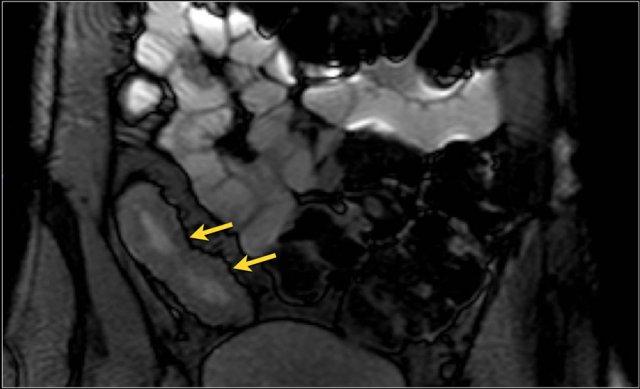

Hình ảnh Balanced FFE mặt phẳng coronal cho thấy rò ruột-bàng quang (mũi tên) xuất phát từ ruột non. Hình ảnh T1W sau tiêm thuốc tương phản cho thấy ngấm thuốc rõ rệt của ruột non và hình ảnh ‘đường ray tàu hỏa’ tại vị trí đường rò.

Rò

Đường xoang và đường rò là các biến chứng thường gặp ở bệnh nhân mắc bệnh Crohn.

Cả hai đều ngấm thuốc rõ rệt trên chuỗi xung T1W sau tiêm gadolinium.

Đường rò có thể biểu hiện dưới dạng cấu trúc phân lớp kiểu ‘đường ray tàu hỏa’ hoặc như một cấu trúc tuyến tính ngấm thuốc.

Đường rò có thể đi từ quai ruột này sang quai ruột khác, đến một tạng rỗng khác hoặc ra da.